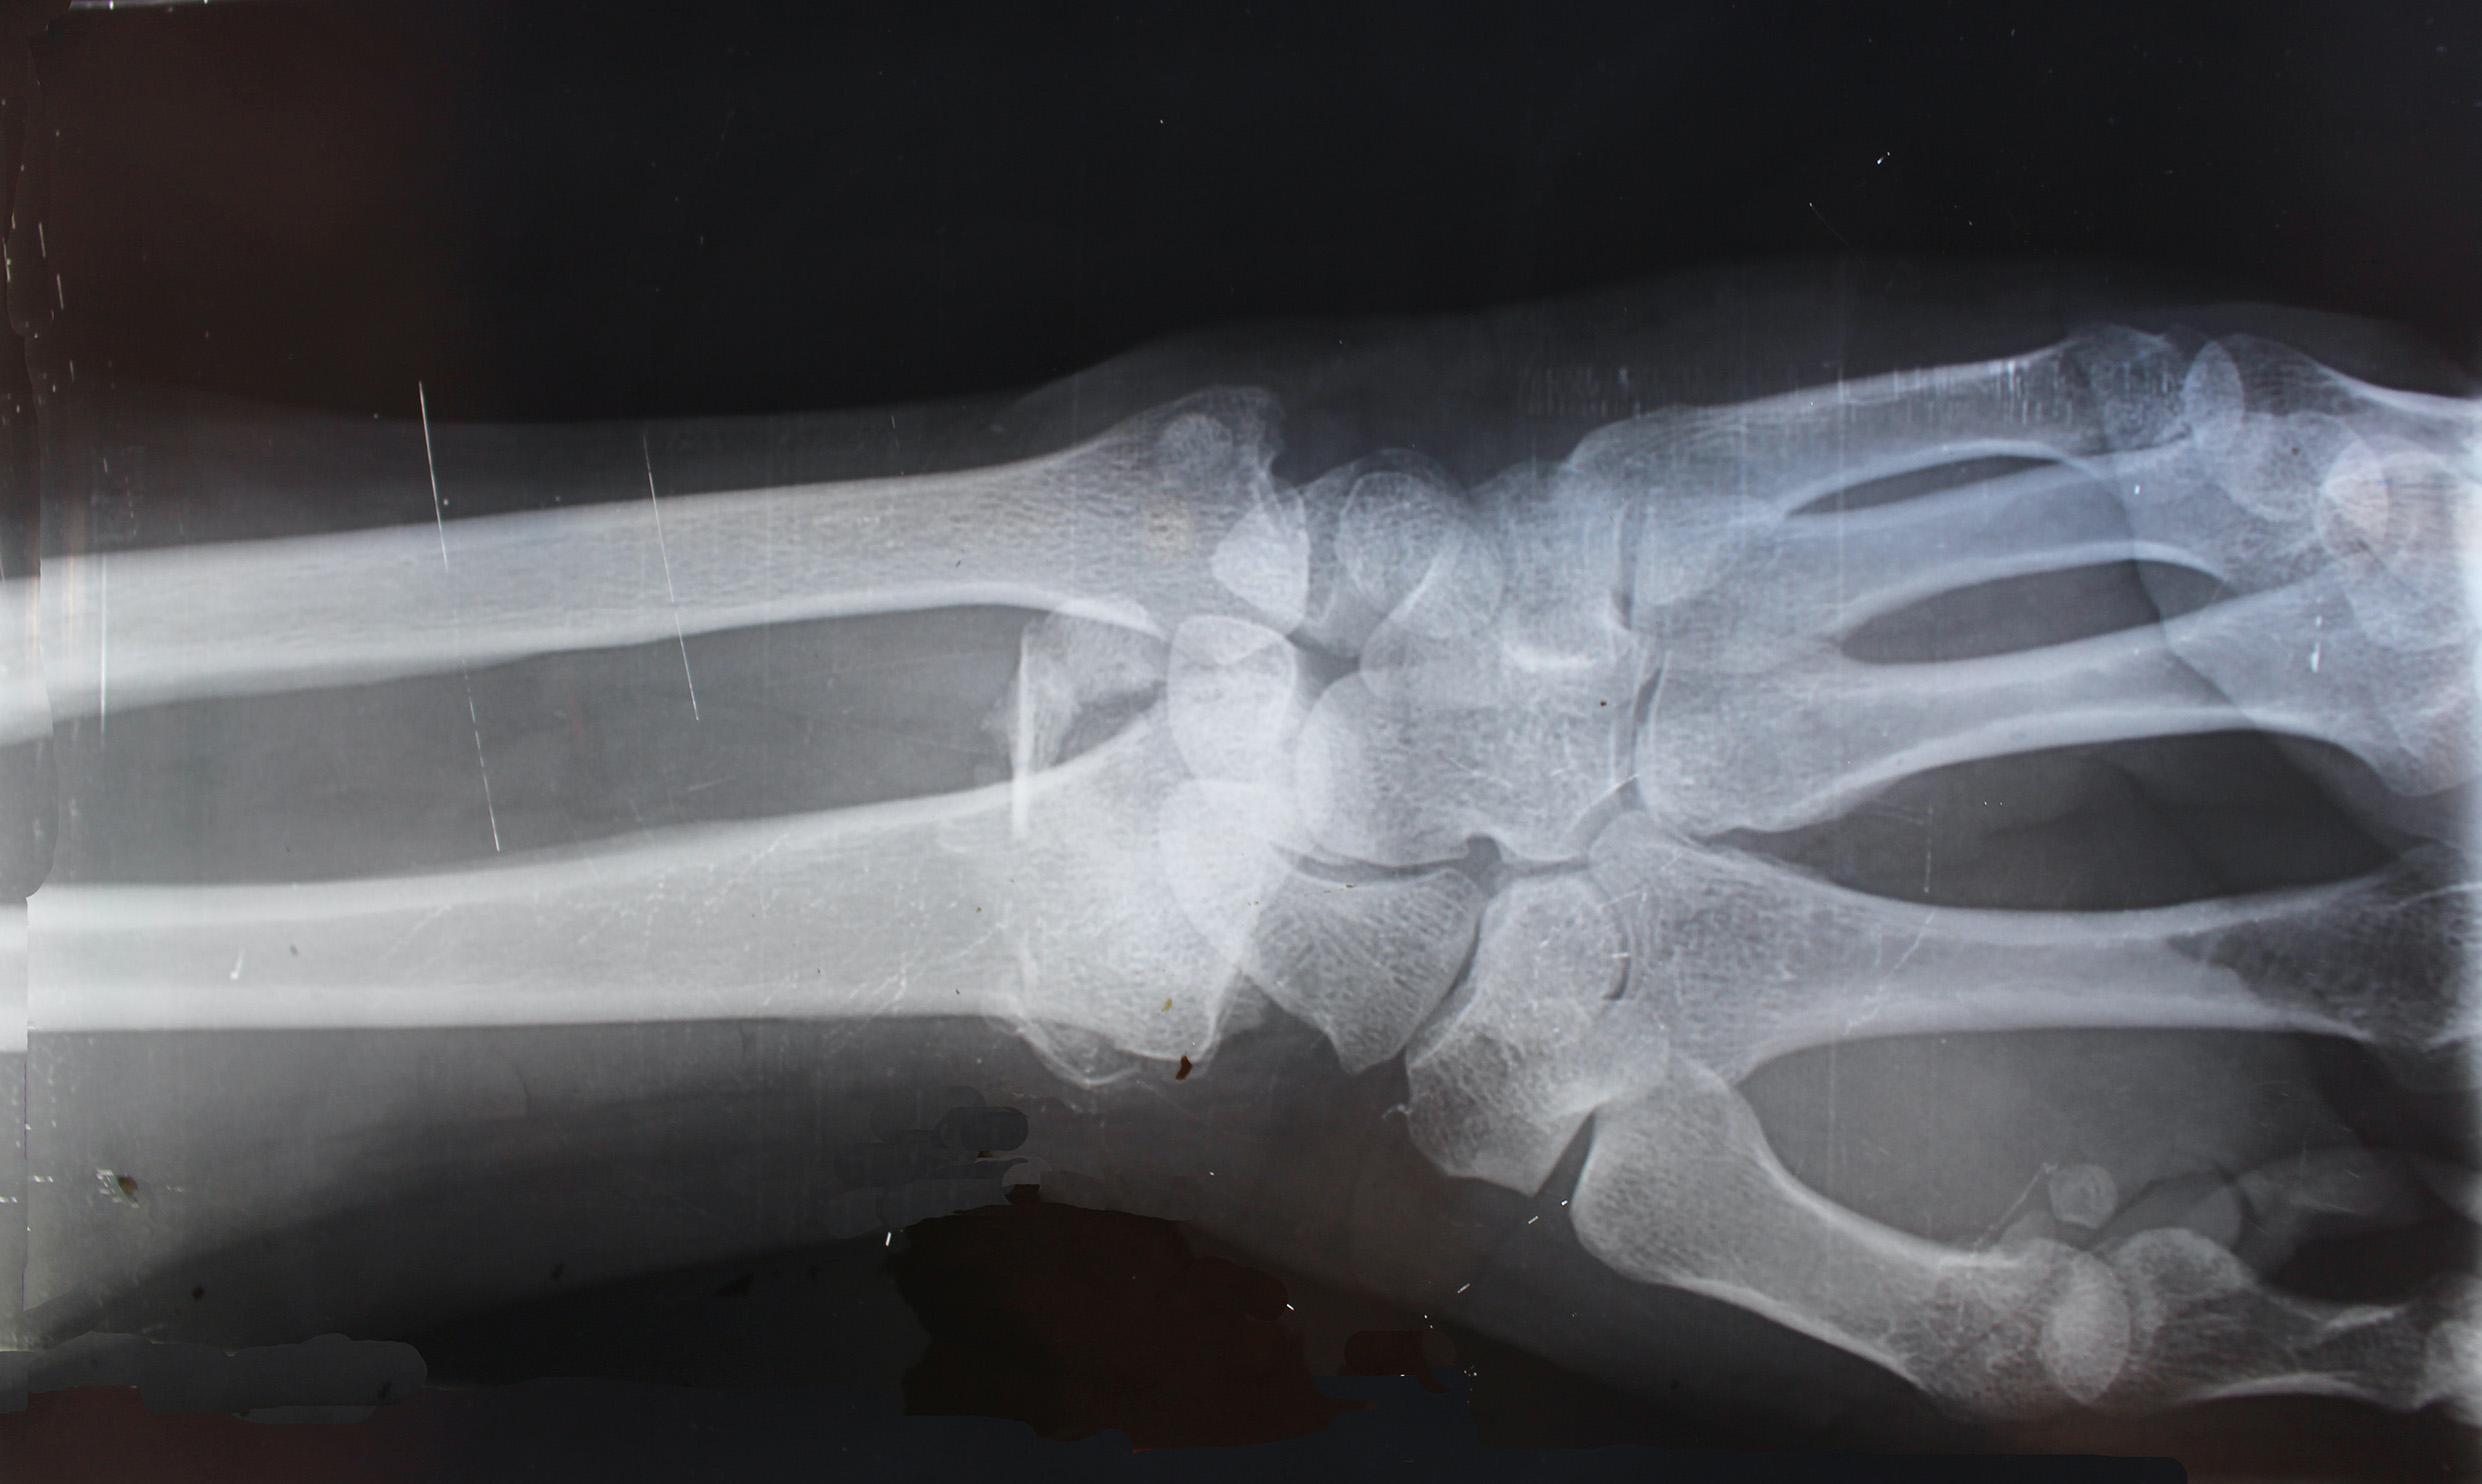

La radiografia del polso è un esame che permette di visualizzare il tessuto osseo e lo scheletro in modo diverso rispetto ai tessuti molli: infatti il tessuto osseo è più compatto e in radiografia appare più chiaro rispetto agli altri tessuti.

La radiografia del polso è di supporto nella diagnosi di:

• Fratture;

• Lussazioni;

• Artrosi;

• Artrite reumatoide;

• Malformazioni ossee congenite.

e viene utilizzata per valutare lo stato di guarigione dell’osso in seguito a fratture oppure in seguito a interventi chirurgici a carico delle ossa (impianti protesici, chiodi, viti e placche.)